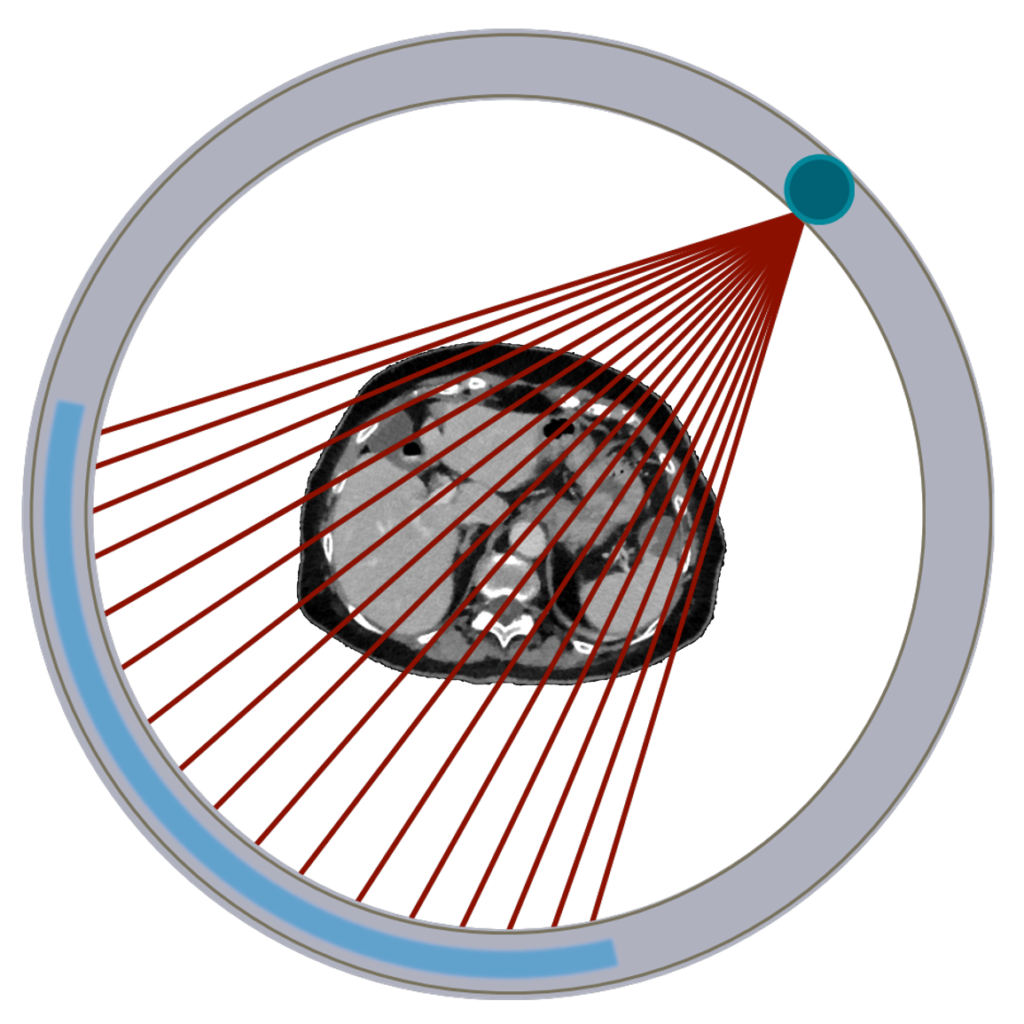

Instrumentation

In the past CT scans were called CAT scans for “computed axial tomography” since axial slices were acquired at multiple locations. Since moving away from strictly “axial” imaging, the “A” has been dropped. CT scans consist of a narrow fan-shaped beam of x-rays. Those x-rays are directed into a subject and some pass through to the opposite side and strike a detector, which can then form an image. The source and detector rotate around subject to acquire projections in ‘every’ direction. These projections are reconstructed into a 3D image.

The x-ray tube and detectors are aligned opposite each other so that the geometry is fixed as they rotate around the patient. This is important when reconstructing the 3D image from projections. The detector is curved to match the curve of the circular motion within the bore. The x-rays are collimated to desired thickness and fan-angle width, which is usually around 60 degrees. One rotation of the system will result in a single axial slice of the patient. The width of this slice depends on the width of the detectors and the collimation used. The patient is moved through the circular aperture (“bore”) while gantry spins 360° sending x-rays through subject to detectors. By moving the patient it is possible to get multiple slices that can then be stacked into a 3D image. Typical bore sizes are 65-80 cm, sometimes larger for radiation therapy applications. For CT systems used to plan radiation therapy, gantries can be tipped up to 30° to allow for non-axial imaging and achieve the desired setup.

To acquire the multiple projections needed to reconstruct a 3D image, the tube and detector must rotate around the gantry. Since a high voltage is needed constantly to produce x-rays and collect signal from the detectors, the system uses a slip ring assembly, where brushes maintain contact with the rings during the rotation. Most CT scanners can do up to 5 rotations per second, which result in high angular velocities and large g-forces. As such, the system needs to be carefully engineered and balanced to maintain these speeds safely. The x-ray tube must also be aligned with the axis of the scanner so that the cathode-anode run parallel to the z-axis. This configuration also allows for the wide (~ 60°) angle of the fan beam. A CT scanner can take 1000 – 3000 projections in a single 0.5 second rotation.

The many projection images are put into sinogram format as they are acquired. The sinograms are a map of the intensity (number of photons) seen by the detector at a given angle and distance from the center. The intensity varies with the amount of attenuation of the photon beam passing through each part of the patient. See the section on image reconstruction for some details. CT typically uses FBP although there is more use of iterative reconstruction in recent years, especially with the push for lower doses, which is better handled with iterative recons.